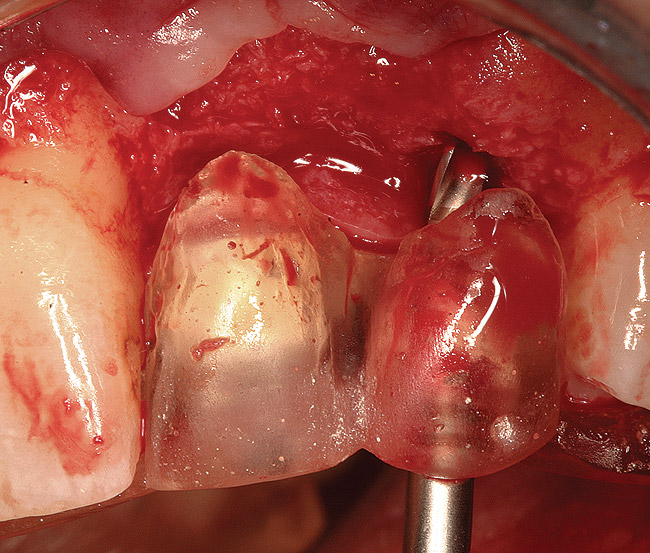

Figure 14  (Case 2) Failed implant at surgical exposure.

Figure 14

Figure 15  (Case 2) Defect after implant removal.

Figure 15